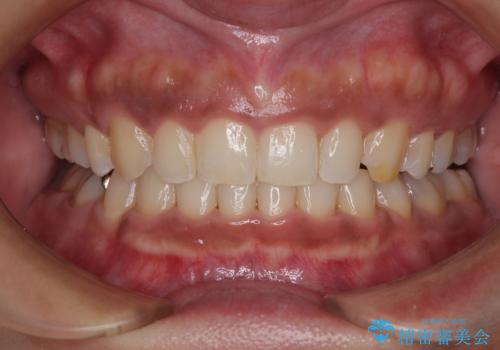

[ セラミック治療 ] 前歯の見た目を改善したい

担当医 大元洋佑

![[ セラミック治療 ] 前歯の見た目を改善したいの症例 治療前](https://seimitsushinbi.jp/wp/wp-content/uploads/2025/10/IMG_9990-2-500x350.jpg?v=1761816440)

![[ セラミック治療 ] 前歯の見た目を改善したいの症例 治療後](https://seimitsushinbi.jp/wp/wp-content/uploads/2025/10/IMG_9934-500x350.jpg?v=1761816431)